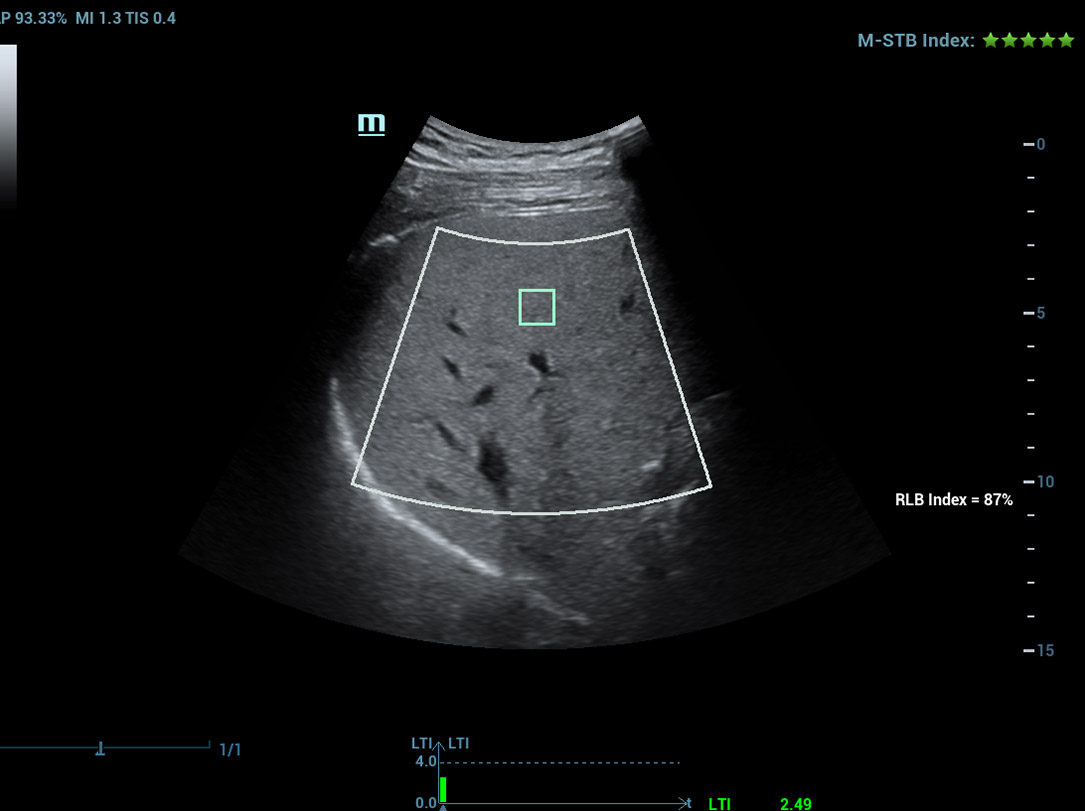

Analisi di laboratorio multiparametriche del fegato grasso

Le analisi di laboratorio multiparametriche del fegato grasso forniscono molteplici strumenti di analisi quantitativa basati su diverse tecnologie acustiche. Consentono di effettuare l'analisi quantitativa della steatosi e migliorano la sensibilitĂ della rilevazione del fegato grasso in fase precoce.